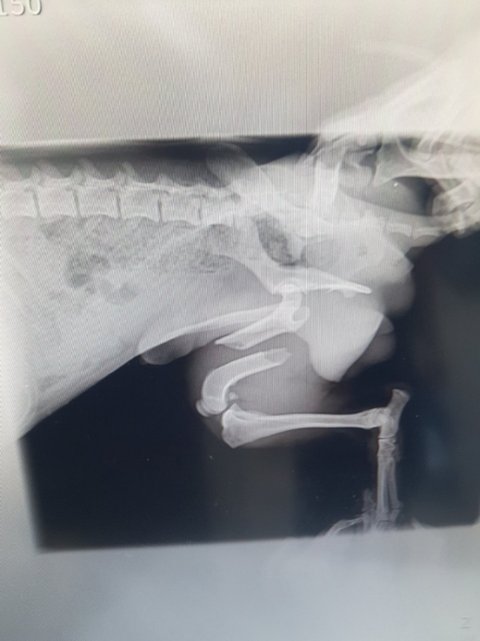

뒷다리골절과 심한사상충으로 고생했던 노아가 멀리 시카고로 가족을 찾아 출국했습니다